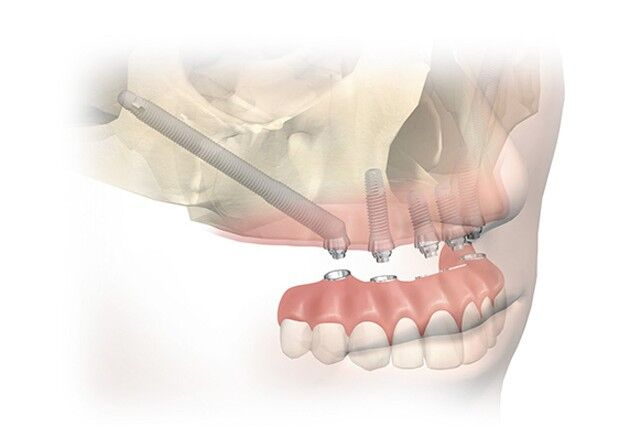

Важно удостовериться, что врач, который берется за процедуру, обладает должным опытом и квалификацией. Мало кто знает, но проводить немедленную нагрузку можно только после специального многоступенчатого обучения в фонде имплантологов и непосредственно в компании-производителе имплантатов. Лучше обращаться к челюстно-лицевым хирургам, которые в совершенстве осведомлены об анатомии черепных костей, поскольку часто работать приходится не просто с челюстной, но и другими лицевыми костями.

Имплантация с применением скуловых имплантатов Zygoma

Стоит обратить внимание и на модели имплантов. Сейчас качественными считаются швейцарские Нобель, Штрауман и Биомед. На подготовительном этапе специалист обязательно должен тщательно проработать все этапы, в том числе, использовать 3D принтер.